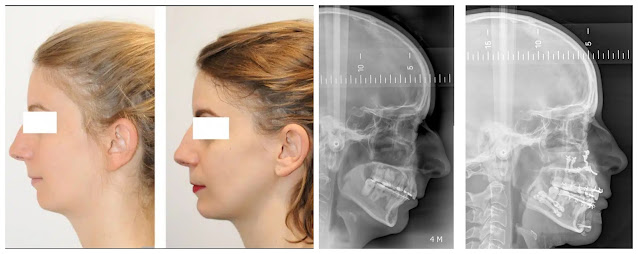

In this trio of pictures, you can see how a wrong diagnosis always turns into the wrong treatment. The girl below had surgery performed on her nose and chin, but the end result isn’t satisfying anyway. Why is that? Because the real cause was not addressed at all. Instead of a nose job combined with the insertion of a chin implant, she needed a jaw surgery with counter-clockwise rotation of both jaws (at the end, I will provide more detailed information on jaw surgery). If you cover the bottom half of the third image, you wouldn't even say the girl has an adenoid face if you did not know beforehand.

The image below shows the appearance of a person before and after the jaw surgery – this type of jaw issue is called CLASS 3 MALOCCLUSION (in the „genetics“ section, I will say more). Remember, NOT A SINGLE JAW ISSUE IS HEREDITARY.

Even though class 3 is not an adenoid face, you can see how much difference it made after the surgeon moved the maxilla forward, providing support for the nasal tissues. There was nothing done to the nose directly.